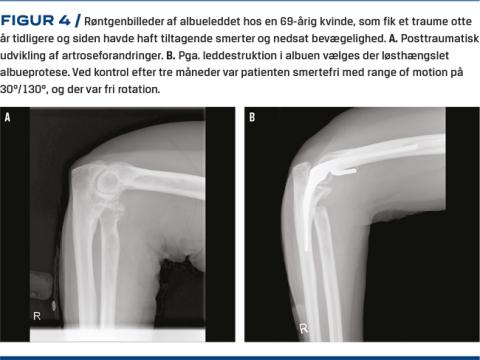

Artrose i albuen kan behandles med artroskopisk eller åben led-løsning med synovektomi, løsning af kapsel og resektion af osseøse prominenser herunder caput radii og ledmus. Herved kan bevægelighed, smerter og aflåsninger bedres. I degenerative led er bedringen oftest forbigående, men kan udskyde tidspunktet for alloplastik. Prognosen ved isolerede bløddelskontrakturer er betydeligt bedre. Ved fremskredne tilfælde med symptomer fra n. ulnaris giver åben kirurgi mulighed for samtidig in situ-løsning af n. ulnaris. Ellers er resultaterne for åben og skopisk operation sammenlignelige [6, 26]. Efterbehandlingen er hurtig guidet mobilisering evt. med passiv udstrækning [6, 26]. Ved svær artrose, hvor andre behandlingstilbud har fejlet, kan albuealloplastik tilbydes [6, 8, 27]. Der findes forskellige alloplastiktyper, der anvendes på forskellige indikationer [8, 27]. Den løst hængslede totalalloplastik er den mest anvendte og fremviser de bedste resultater ved artrose (Figur 4) [7, 27, 28]. Efterbehandling er oftest kort immobilisering i bandage, efterfulgt af fri guidet mobilisering. 90% oplever lindring af smerterne, men må acceptere vægtrestriktion for ekstremiteten. Tiårsproteseoverlevelsen er i europæiske studier 80-85% [8, 27, 28]. Proteseløsning, fraktur, dyb infektion og n. ulnaris-påvirkning er de hyppigste komplikationer, der ses i op til 20% af tilfældene [8, 29, 30].